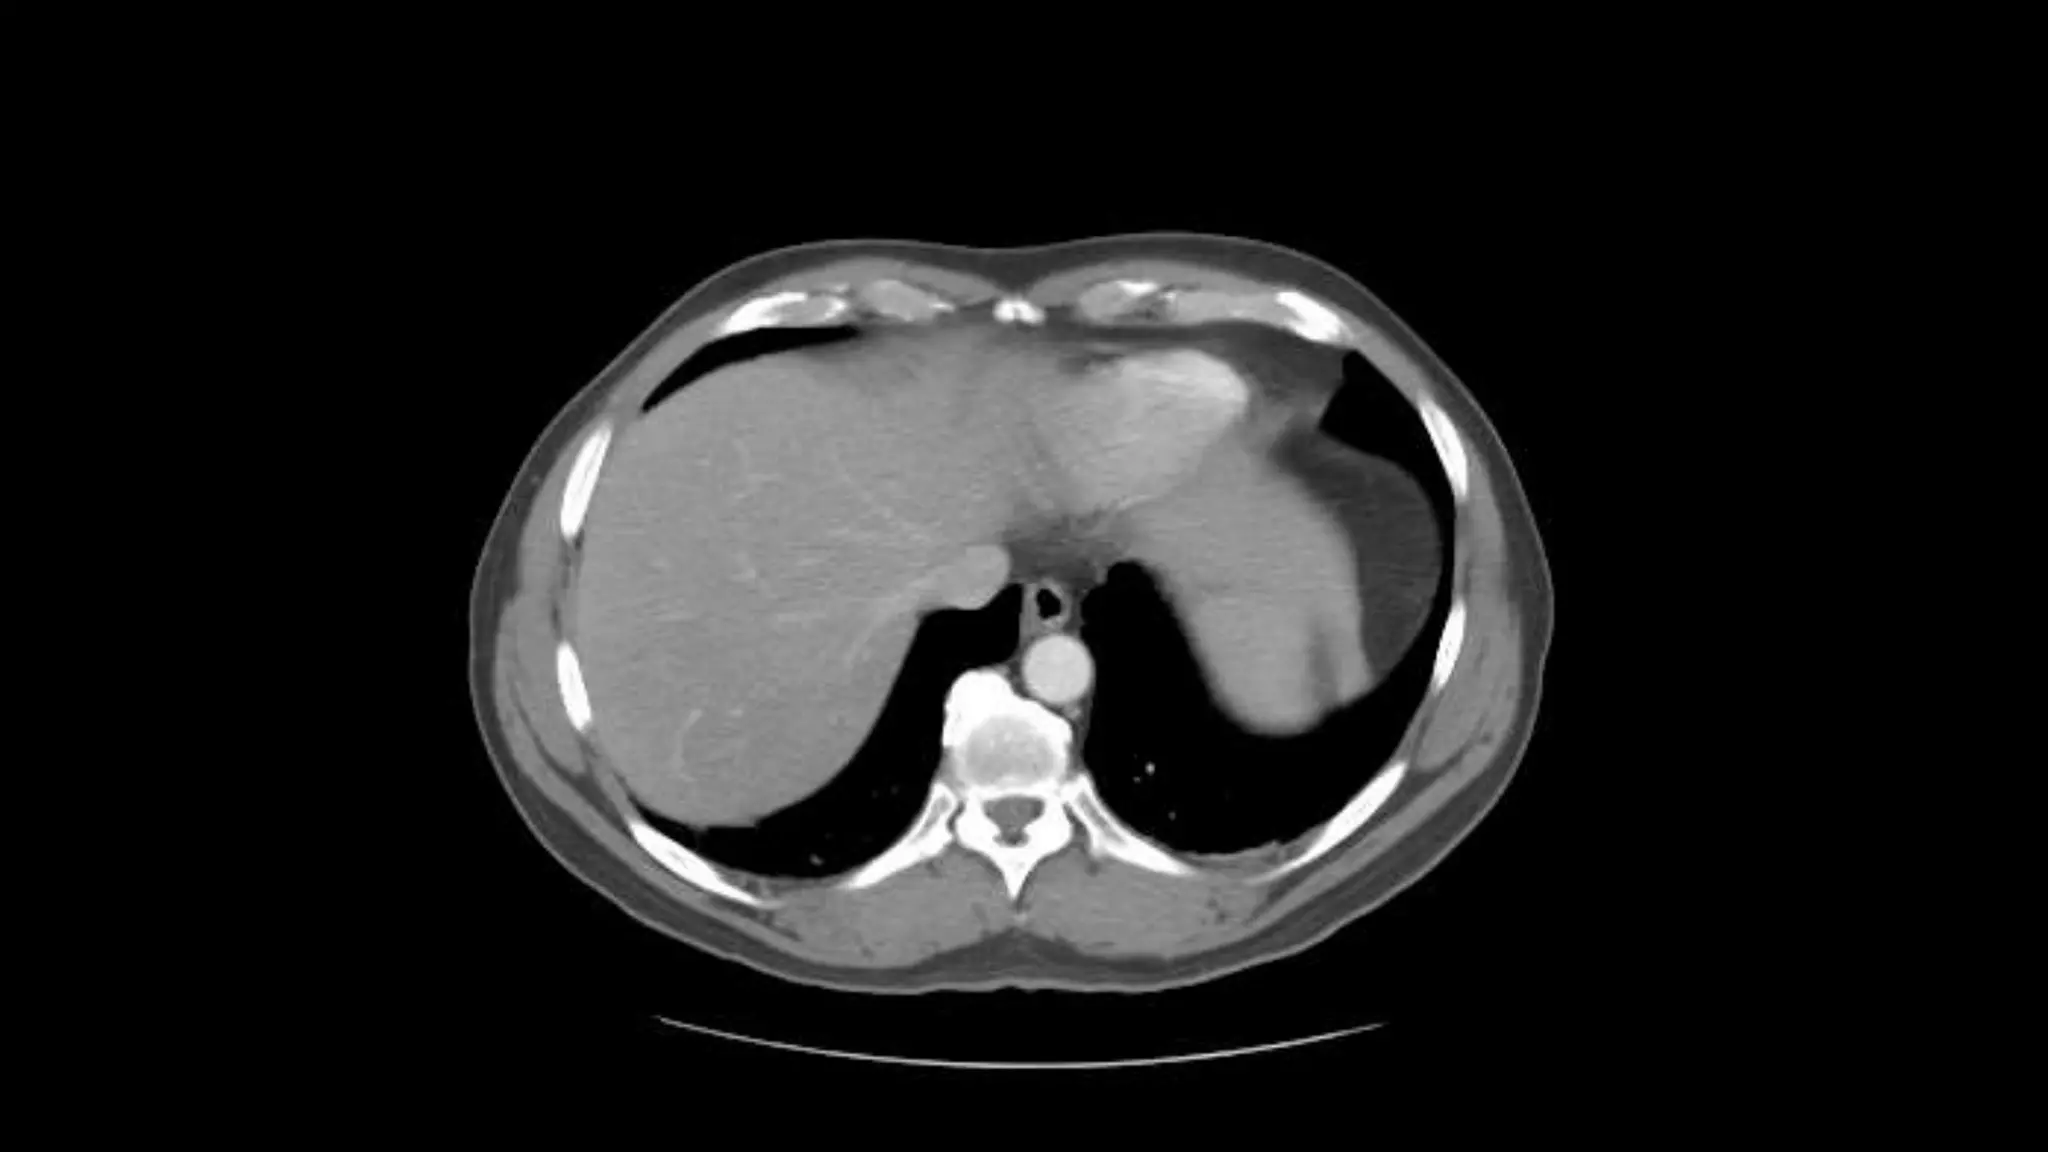

 In this sequence of images, we will label the abdominal vasculature.

The CT images are 5mm slices with soft tissue window settings. IV

 IMAGES ARE VIEWED AS LOOKING FROM THE FEET

RIGHT LEFT

Follow the IV contrast filled Aorta as we descend caudally. Branches and points

of interest will be noted.

This is an excellent image of the right, middle and left hepatic veins draining into the Inferior

Vena Cava. Don’t confuse this structure with the IVC, this is the esophagus at the level of the

Lower esophageal sphincter, page up and down to confirm this.

The outline of the Inferior Vena Cava is more

distinct in this image.